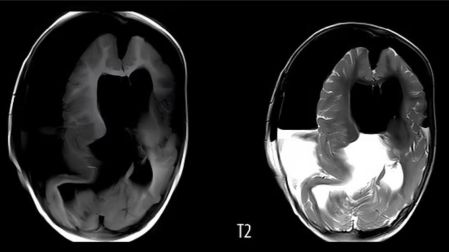

Los médicos le realizaron una tomografía computarizada de la cabeza y descubrieron una masa de 13 centímetros de diámetro en el cráneo, apenas más grande que una pelota de béisbol. Dentro de la masa había grandes trozos de hueso.

Al intentar extirparlo, los médicos descubrieron que el feto tenía columna vertebral y huesos, y el comienzo de una boca, ojos, cabello, antebrazos, manos y pies. Medía 18 centímetros de largo.

El gemelo provocó una "grave compresión del tejido cerebral" de la bebé, por lo que la pequeña nunca despertó de la cirugía y estuvo conectada a un respirador artificial mientras sufría convulsiones después de la operación.

Doce días después de la cirugía, la familia decidió desconectarla del soporte vital.

Los médicos indicaron que la pequeña presentaba una inflamación severa en la cabeza y retrasos en su desarrollo, lamentablemente, la condición era tan grave que la niña falleció quince días después de la operación, ya que el daño en su cerebro era demasiado extenso para sobrevivir.

Este fenómeno extremadamente raro, conocido científicamente como “fetus in fetus”, ocurre en aproximadamente 1 de cada 500 mil nacimientos. Dentro del cráneo, solo se han documentado 18 casos de esta inusual afección.